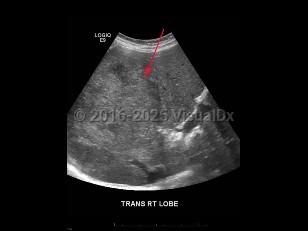

Hepatocellular carcinoma (HCC) is the most common primary malignancy of the liver in adults over the age of 65 years worldwide and is considered the third leading cause of cancer death. In the United States, the ratio of incidence of HCC between men and women is 2.5 to 1. The incidence and sex ratio of HCC varies regionally, and the majority of cases are diagnosed in developing nations. The incidence of HCC is highest in East Asia, Southeast Asia, and sub-Saharan Africa where disease is most commonly associated with chronic viral

C infection. Major risk factors for developing HCC include

cirrhosis, chronic viral hepatitis, dietary aflatoxin,

alcohol abuse. Children are rarely affected; the only known risk factor in this population is chronic hepatitis B carrier status. In the United States, data suggests that the incidence of HCC may have remained stable since 2013, which may be attributed to improvements in antiviral therapy.